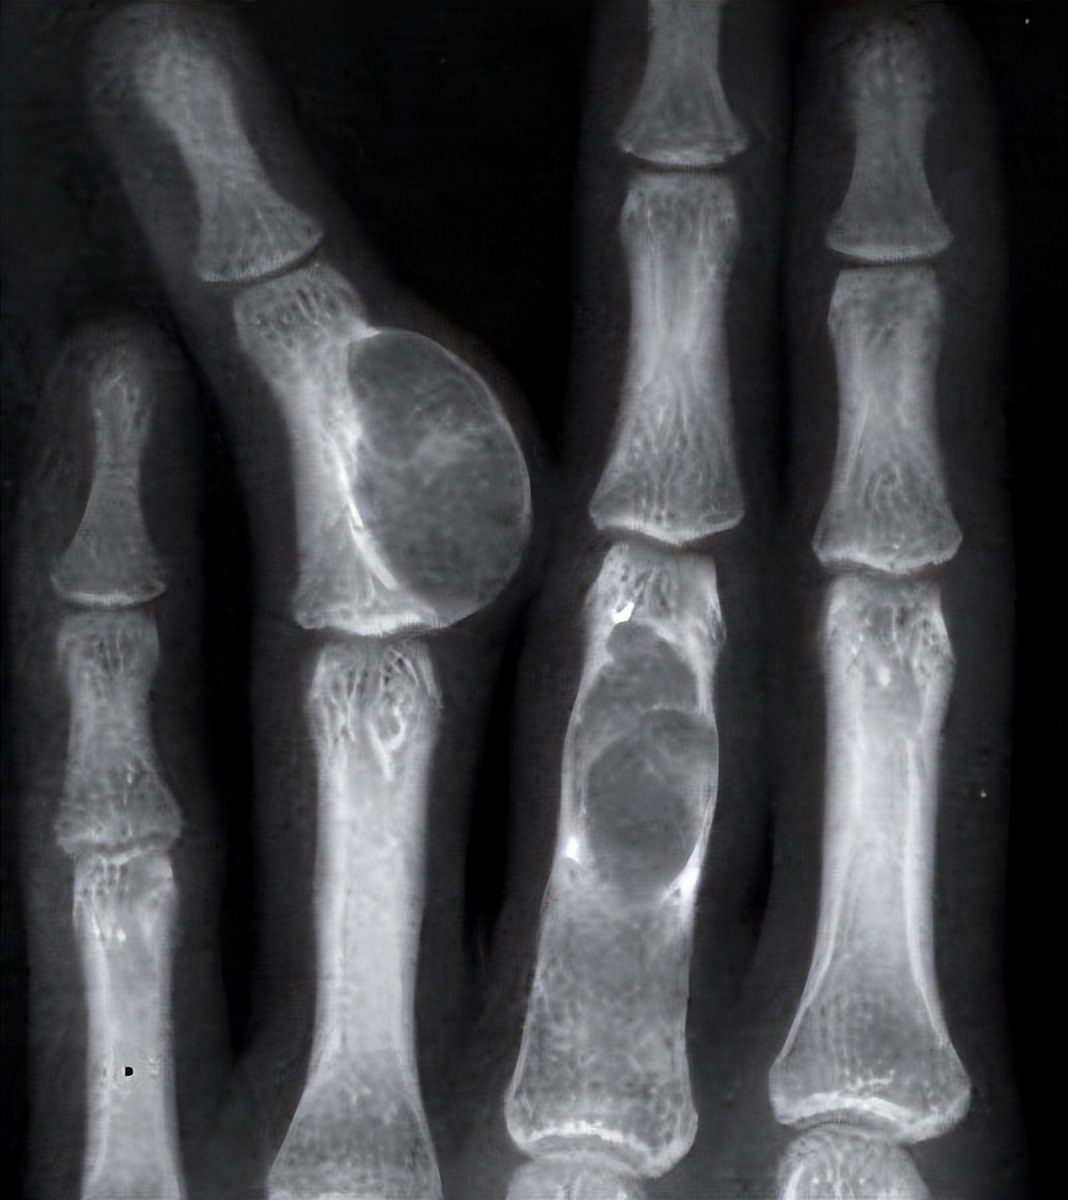

经过检查之后,医生表示李明鑫的腿可能是骨肉瘤造成的。

骨肉瘤也叫成骨肉瘤,是一种比较常见的发生在20岁以下的青少年或儿童的一种恶性骨肿瘤。

在李明鑫四次放疗结束后,医生发现她腿上的癌细胞,还在不停地扩散,如果不能阻止的话,她将会受到生命危险。

医生发现之后立马把这个事实告诉了李明鑫的父母,并且提出了唯一的解决办法,那就是——截肢。